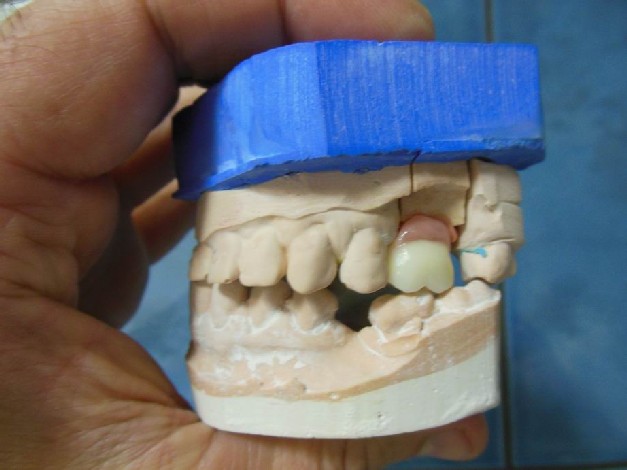

Przykłady implantologii

Zastosowanie implantoprotetyki w przypadku gdy klasyczna protetyka nie sprawdza się.